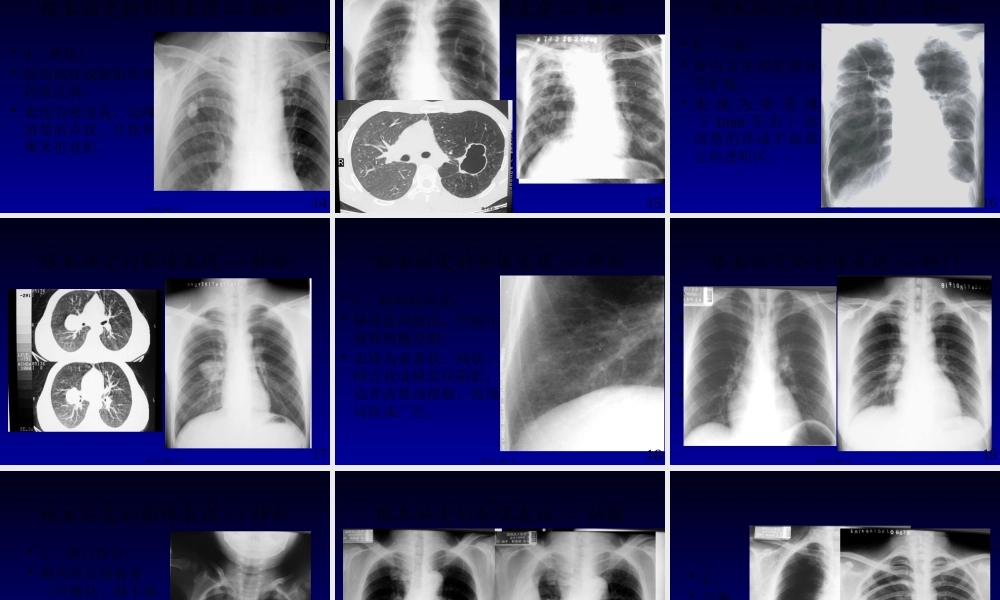

呼吸系统影像学诊断-----根本病变广东省人民医院影像医学部放射科赵振军1第一页,共四十一页。本节课内容•肺部根本病变的影像表现〔X线和CT〕•支气管病变•肺部病变•渗出性,增殖性、纤维化、钙化、空洞及空腔、肿块、肺间质的变化。•胸膜病变•纵隔病变•膈病变2第二页,共四十一页。根本病变的影像表现---支气管•一、支气管阻塞性改变•原因:1、支气管腔内。2、腔外。•支气管阻塞最常见病因有支气管腔内肿瘤、异物、结核及先天狭窄等。•淋巴结肿大是支气管外压性狭窄最常见的原因。•可引起阻塞性肺气肿、肺炎、肺不张。3第三页,共四十一页。根本病变的影像表现---支气管•1、阻塞性肺气肿:•支气管活瓣性狭窄,肺含气量增多。•分弥漫性和局限性•表现为1、肺透明度加大。2、肺纹理稀疏。3、占位改变:肋间隙增宽,膈肌下降、纵隔对侧移位等。4第四页,共四十一页。根本病变的影像表现---支气管•2、阻塞性肺炎:•支气管阻塞后继发肺部炎症。•A、阻塞区出现斑片状模糊影•B、该影特征为反复在固定部位出现•C、治疗吸收缓慢。5第五页,共四十一页。根本病变的影像表现---支气管•3、阻塞性肺不张:•支气管完全阻塞,肺内气体吸收,肺体积缩小。•一般分一侧肺、肺叶、肺段和肺小叶不张。6第六页,共四十一页。•直接征象:病变区域均匀密度增高影。•间接征象:体积收缩,如胸廓塌陷,肋间隙变窄,纵隔向患侧移位,肺门移位和膈肌升高等。根本病变的影像表现---不张7第七页,共四十一页。•轮廓征根本病变的影像表现---中叶不张8第八页,共四十一页。•“S征〞•反写“S〞根本病变的影像表现---不张9第九页,共四十一页。根本病变的影像表现---肺部•二、肺部病变•1、渗出性病变:•肺泡内气体被渗出液和少量细胞取代。•表现为边缘模糊的密度增高影。10第十页,共四十一页。•斑片、模糊•腺泡内渗出呈斑点状;•小叶渗出为斑片状;•肺段和肺叶渗出为大片状实变影,影内可见支气管气像。11第十一页,共四十一页。根本病变的影像表现---肺部•2、增殖性病变:•肺泡内细胞积聚,可形成肉芽肿。•表现为边缘较清楚的密度增高影,呈结节状、球形或肿块状。12第十二页,共四十一页。根本病变的影像表现---肺部•3、纤维化:•肺组织被纤维组织取代。•表现为结节状、索条状和斑块状等,但边缘清楚,高密度影。•纤维化可引起肺门及纵隔向患区移位,肋间隙狭窄,膈肌升高等。13第十三页,共四十一页。根本病变的影像表现---肺部•4、...